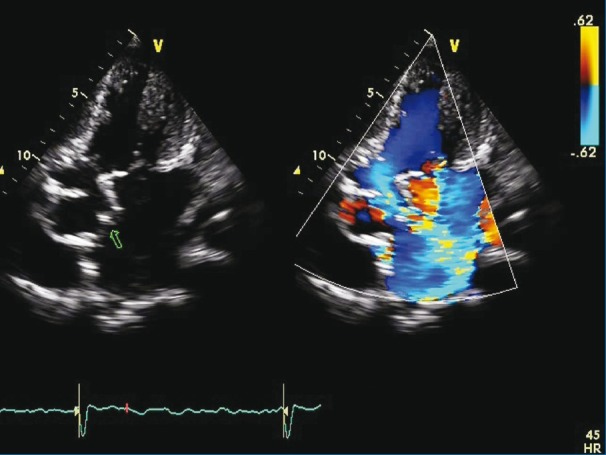

Mitral Aortic Intervalvular Fibrosa MAIF

Fibrous region of the heart that connects the anterior mitral leaflet to the posterior aortic root and communicates with the left ventricular outflow tract

MAIF Pseudoaneurysm